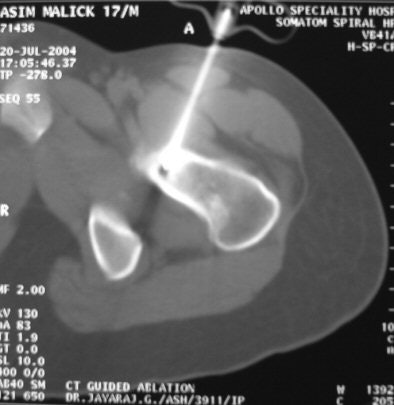

| RF ablation being performed under CT guidance. |

In the procedure Govindaraj performed, CT was used to localise the lesion, and axial slices of 2-mm thickness were obtained. Percutaneous RF ablation was performed under CT guidance, the RF probe was introduced into the nidus, and the tumour tissues were heated to a temperature of 100 degrees centigrade for three to five minutes.

The unit used for the procedure was a Model 1500X RF generator and a Starburst SDE 16.5-gauge probe (RITA Medical Systems, Mountain View, CA).

The ablation was done two to three times at different angles for close to half an hour. The entire procedure takes about two hours. "The immediate effect is not apparent on CT, but when the patient recovers from anaesthesia, he is pain-free," Govindaraj told AuntMinnieIndia.com in an interview.